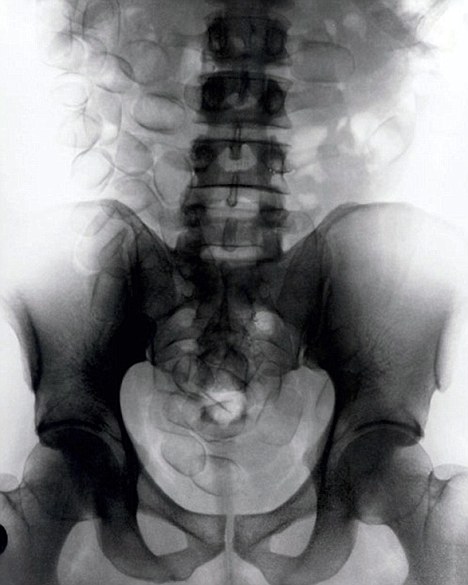

現(xiàn)年30歲的菲達(dá)利斯(Fidelis Ozouli)冒著生命危險將重達(dá)1公斤的毒品吞下,被抓后卻辯稱不知道吞下的是毒品。當(dāng)時,曼徹斯特機(jī)場的海關(guān)人員看到毒販菲達(dá)利斯臃腫的肚腩,顯得很不自然,于是開始懷疑。檢查人員用X射線機(jī)照他的胃部時,發(fā)現(xiàn)了大量可卡因。目前他已被送往附近醫(yī)院,以確保排出所有的毒品。

這名男子還將毒品藏在幾十個避孕套里,估計(jì)純度為78%,價值25萬英鎊。毒販后來被帶到曼徹斯特皇家法庭,自稱來自尼日利亞,目前在倫敦生活和學(xué)習(xí)。他承認(rèn)攜帶A類毒品入關(guān)確實(shí)犯了法,但否認(rèn)他吞下的是毒品。目前他已經(jīng)被英國警方正式逮捕,案件已轉(zhuǎn)交給毒品稽查部門,預(yù)計(jì)他將被判入獄10年。